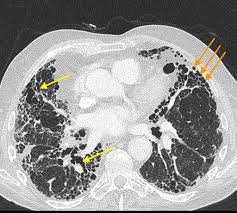

Both of these colored arrows indicate the same disease, with the yellow arrow being called this finding

What is traction bronchiectasis (must be specific!)?

*The orange arrows is honeycombing (smaller clusters as opposed to larger/longer tears), both representing idiopathic pulmonary fibrosis (IPF)